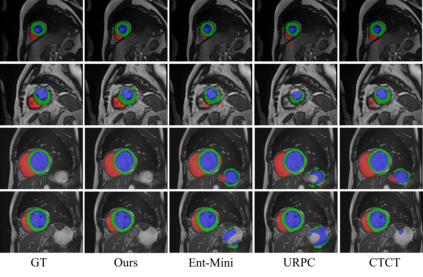

Semi-supervised medical image segmentation has attracted much attention in recent years because of the high cost of medical image annotations. In this paper, we propose a novel Inherent Consistent Learning (ICL) method, which aims to learn robust semantic category representations through the semantic consistency guidance of labeled and unlabeled data to help segmentation. In practice, we introduce two external modules namely Supervised Semantic Proxy Adaptor (SSPA) and Unsupervised Semantic Consistent Learner (USCL) that based on the attention mechanism to align the semantic category representations of labeled and unlabeled data, as well as update the global semantic representations over the entire training set. The proposed ICL is a plug-and-play scheme for various network architectures and the two modules are not involved in the testing stage. Experimental results on three public benchmarks show that the proposed method can outperform the state-of-the-art especially when the number of annotated data is extremely limited. Code is available at: https://github.com/zhuye98/ICL.git.